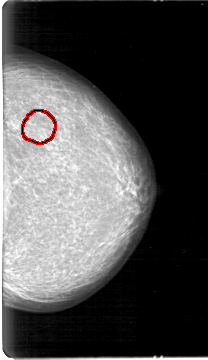

D_4026_1.RIGHT_MLO

LEFT_MLO LINES 5386 PIXELS_PER_LINE 3181 BITS_PER_PIXEL 12 RESOLUTION 43.5 OVERLAY

FILE: D_4026_1.LEFT_MLO.OVERLAY

TOTAL_ABNORMALITIES 1

ABNORMALITY 1

LESION_TYPE MASS SHAPE OVAL MARGINS OBSCURED

ASSESSMENT 0

SUBTLETY 3

PATHOLOGY BENIGN

TOTAL_OUTLINES 1

BOUNDARY